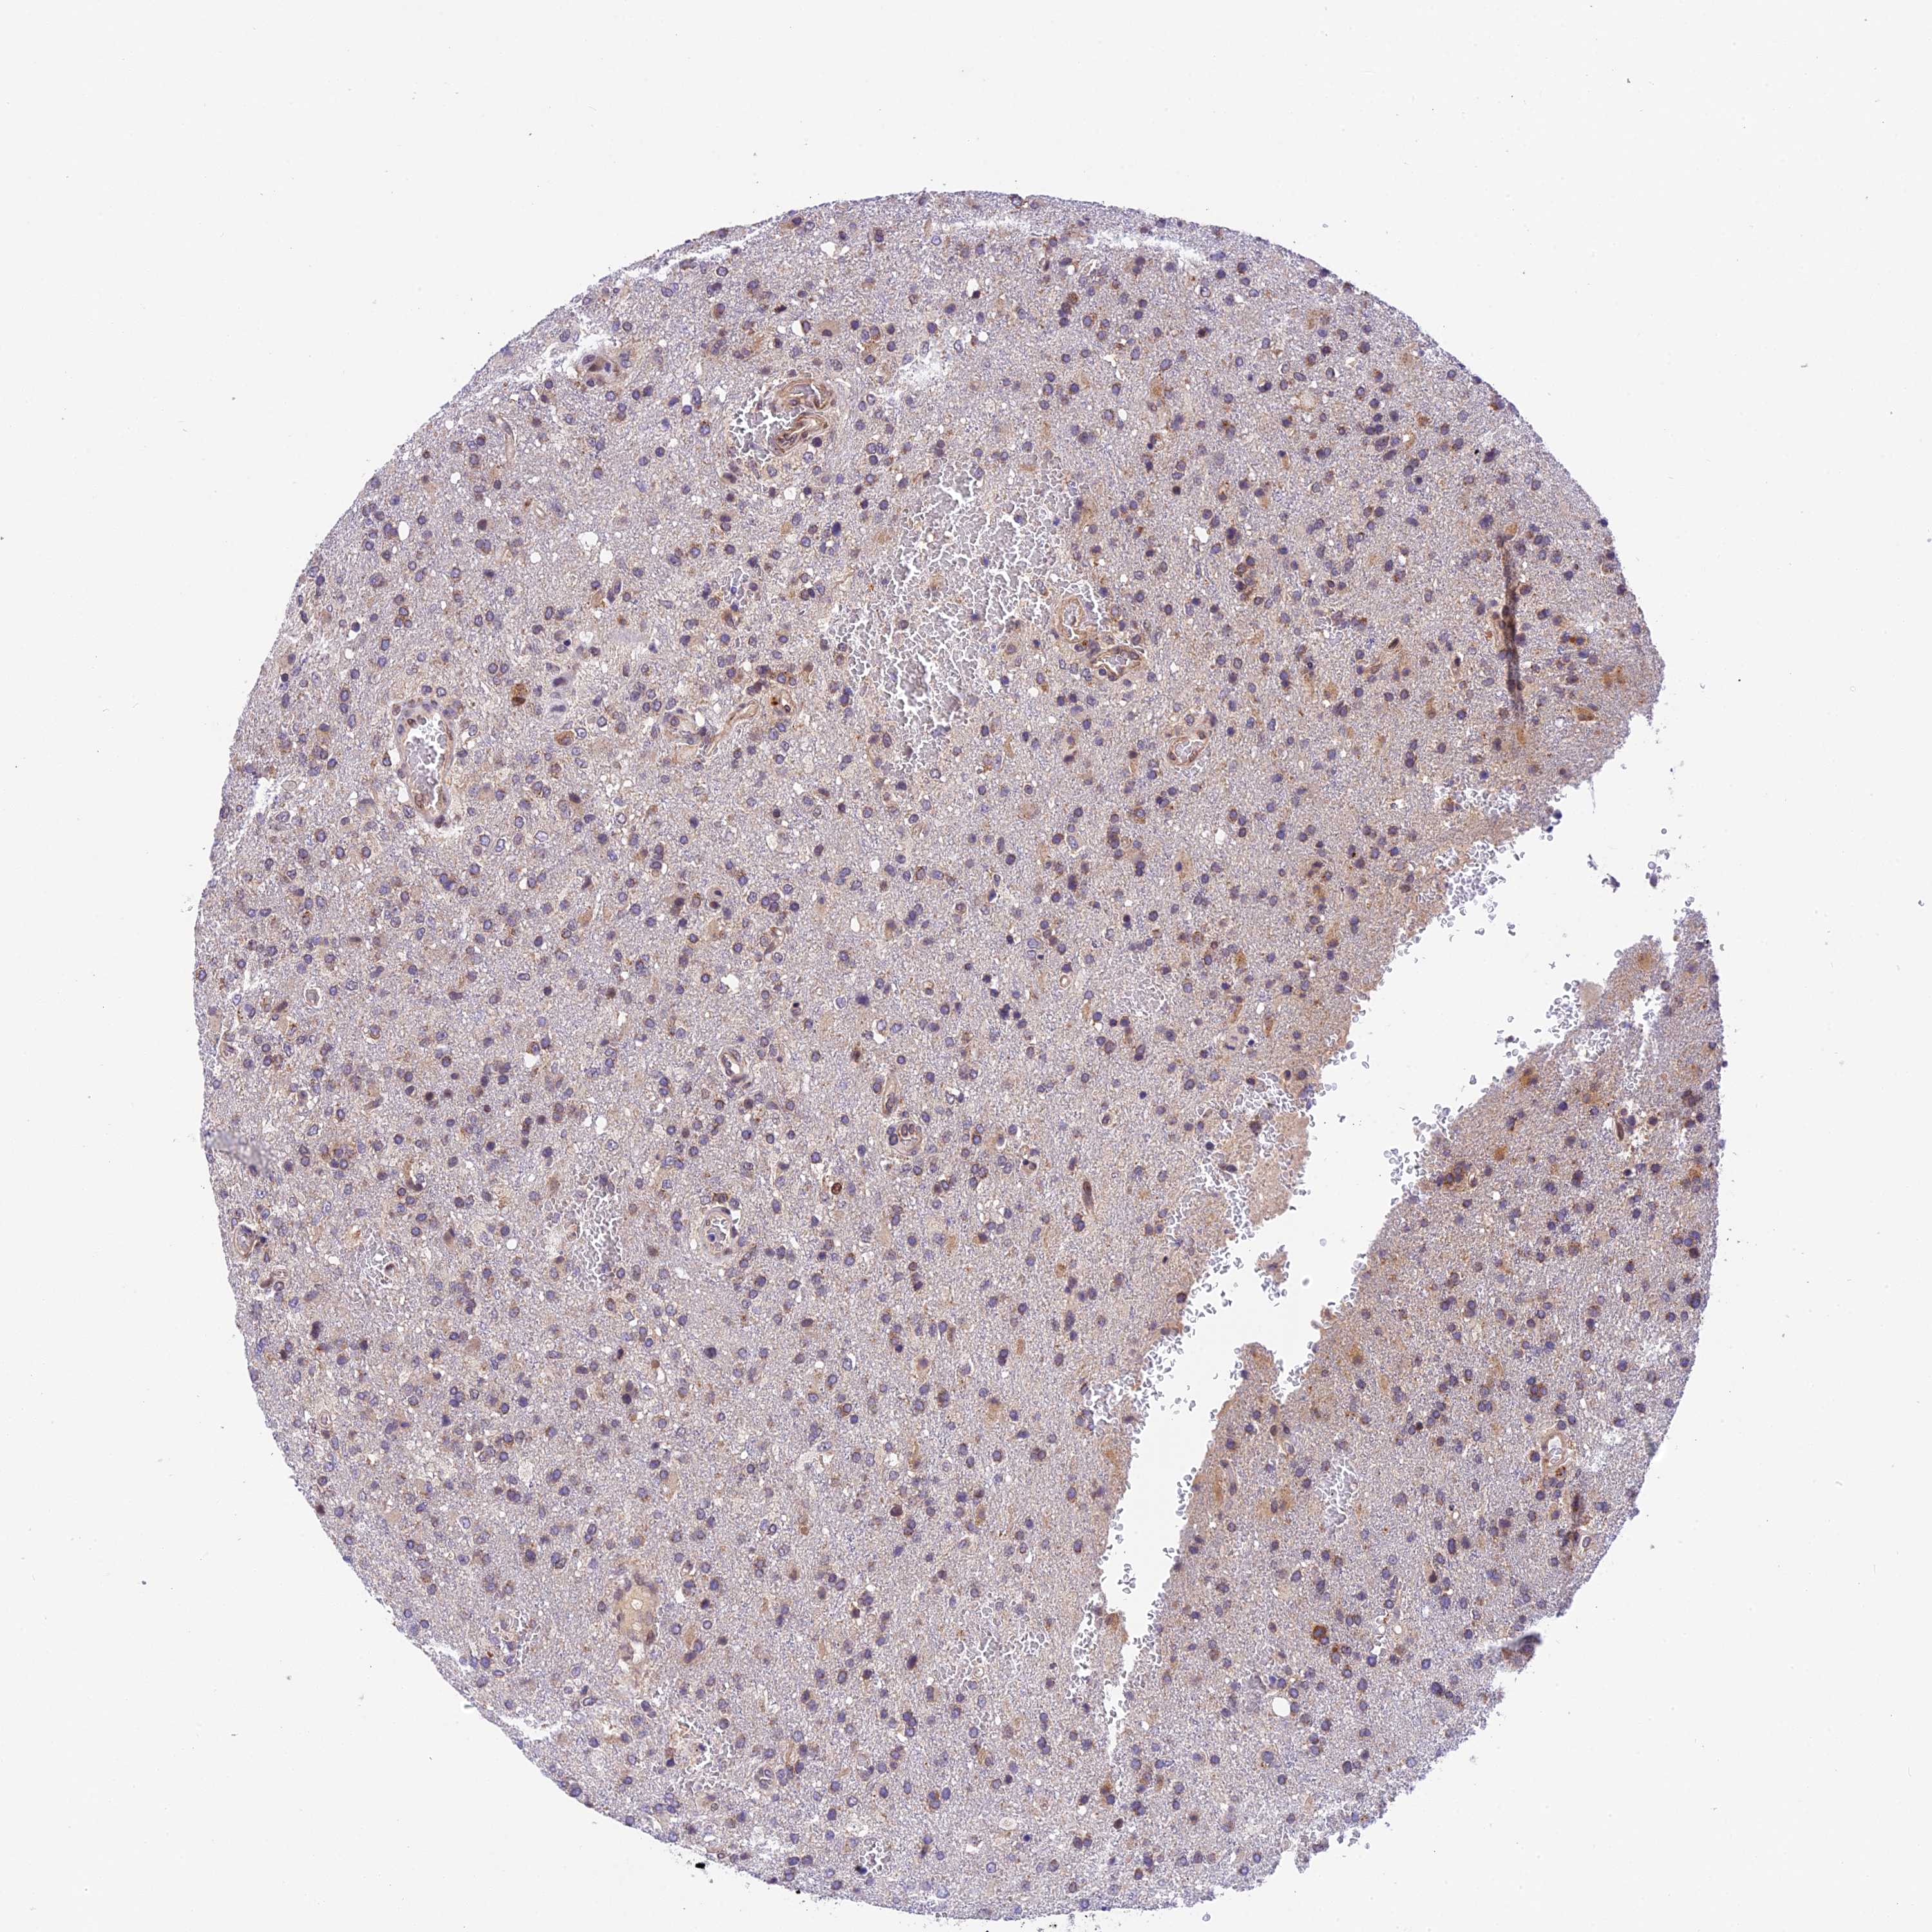

GLIOMA - Protein expressioni

A mouse-over function shows sample information and annotation data. Click on an image to view it in a full screen mode. Samples can be filtered based on level of antibody staining by selecting one or several of the following categories: high, medium, low and not detected. The assay and annotation is described here.

Note that samples used for immunohistochemistry by the Human Protein Atlas do not correspond to samples in the TCGA dataset.

Antibody stainingi

Antibody staining in the annotated cell types in the current human tissue is reported as not detected, low, medium, or high, based on conventional immunohistochemistry profiling in selected tissues. This score is based on the combination of the staining intensity and fraction of stained cells.

Each image is clickable and will lead to virtual microscopy that enables deeper exploration of all samples and also displays staining intensity scores, fraction scores and subcellular localization as well as patient and tissue information for each sample.

Antibody HPA041880

Antibody HPA054709

Glioma, malignant, High grade

Glioma, malignant, Low grade